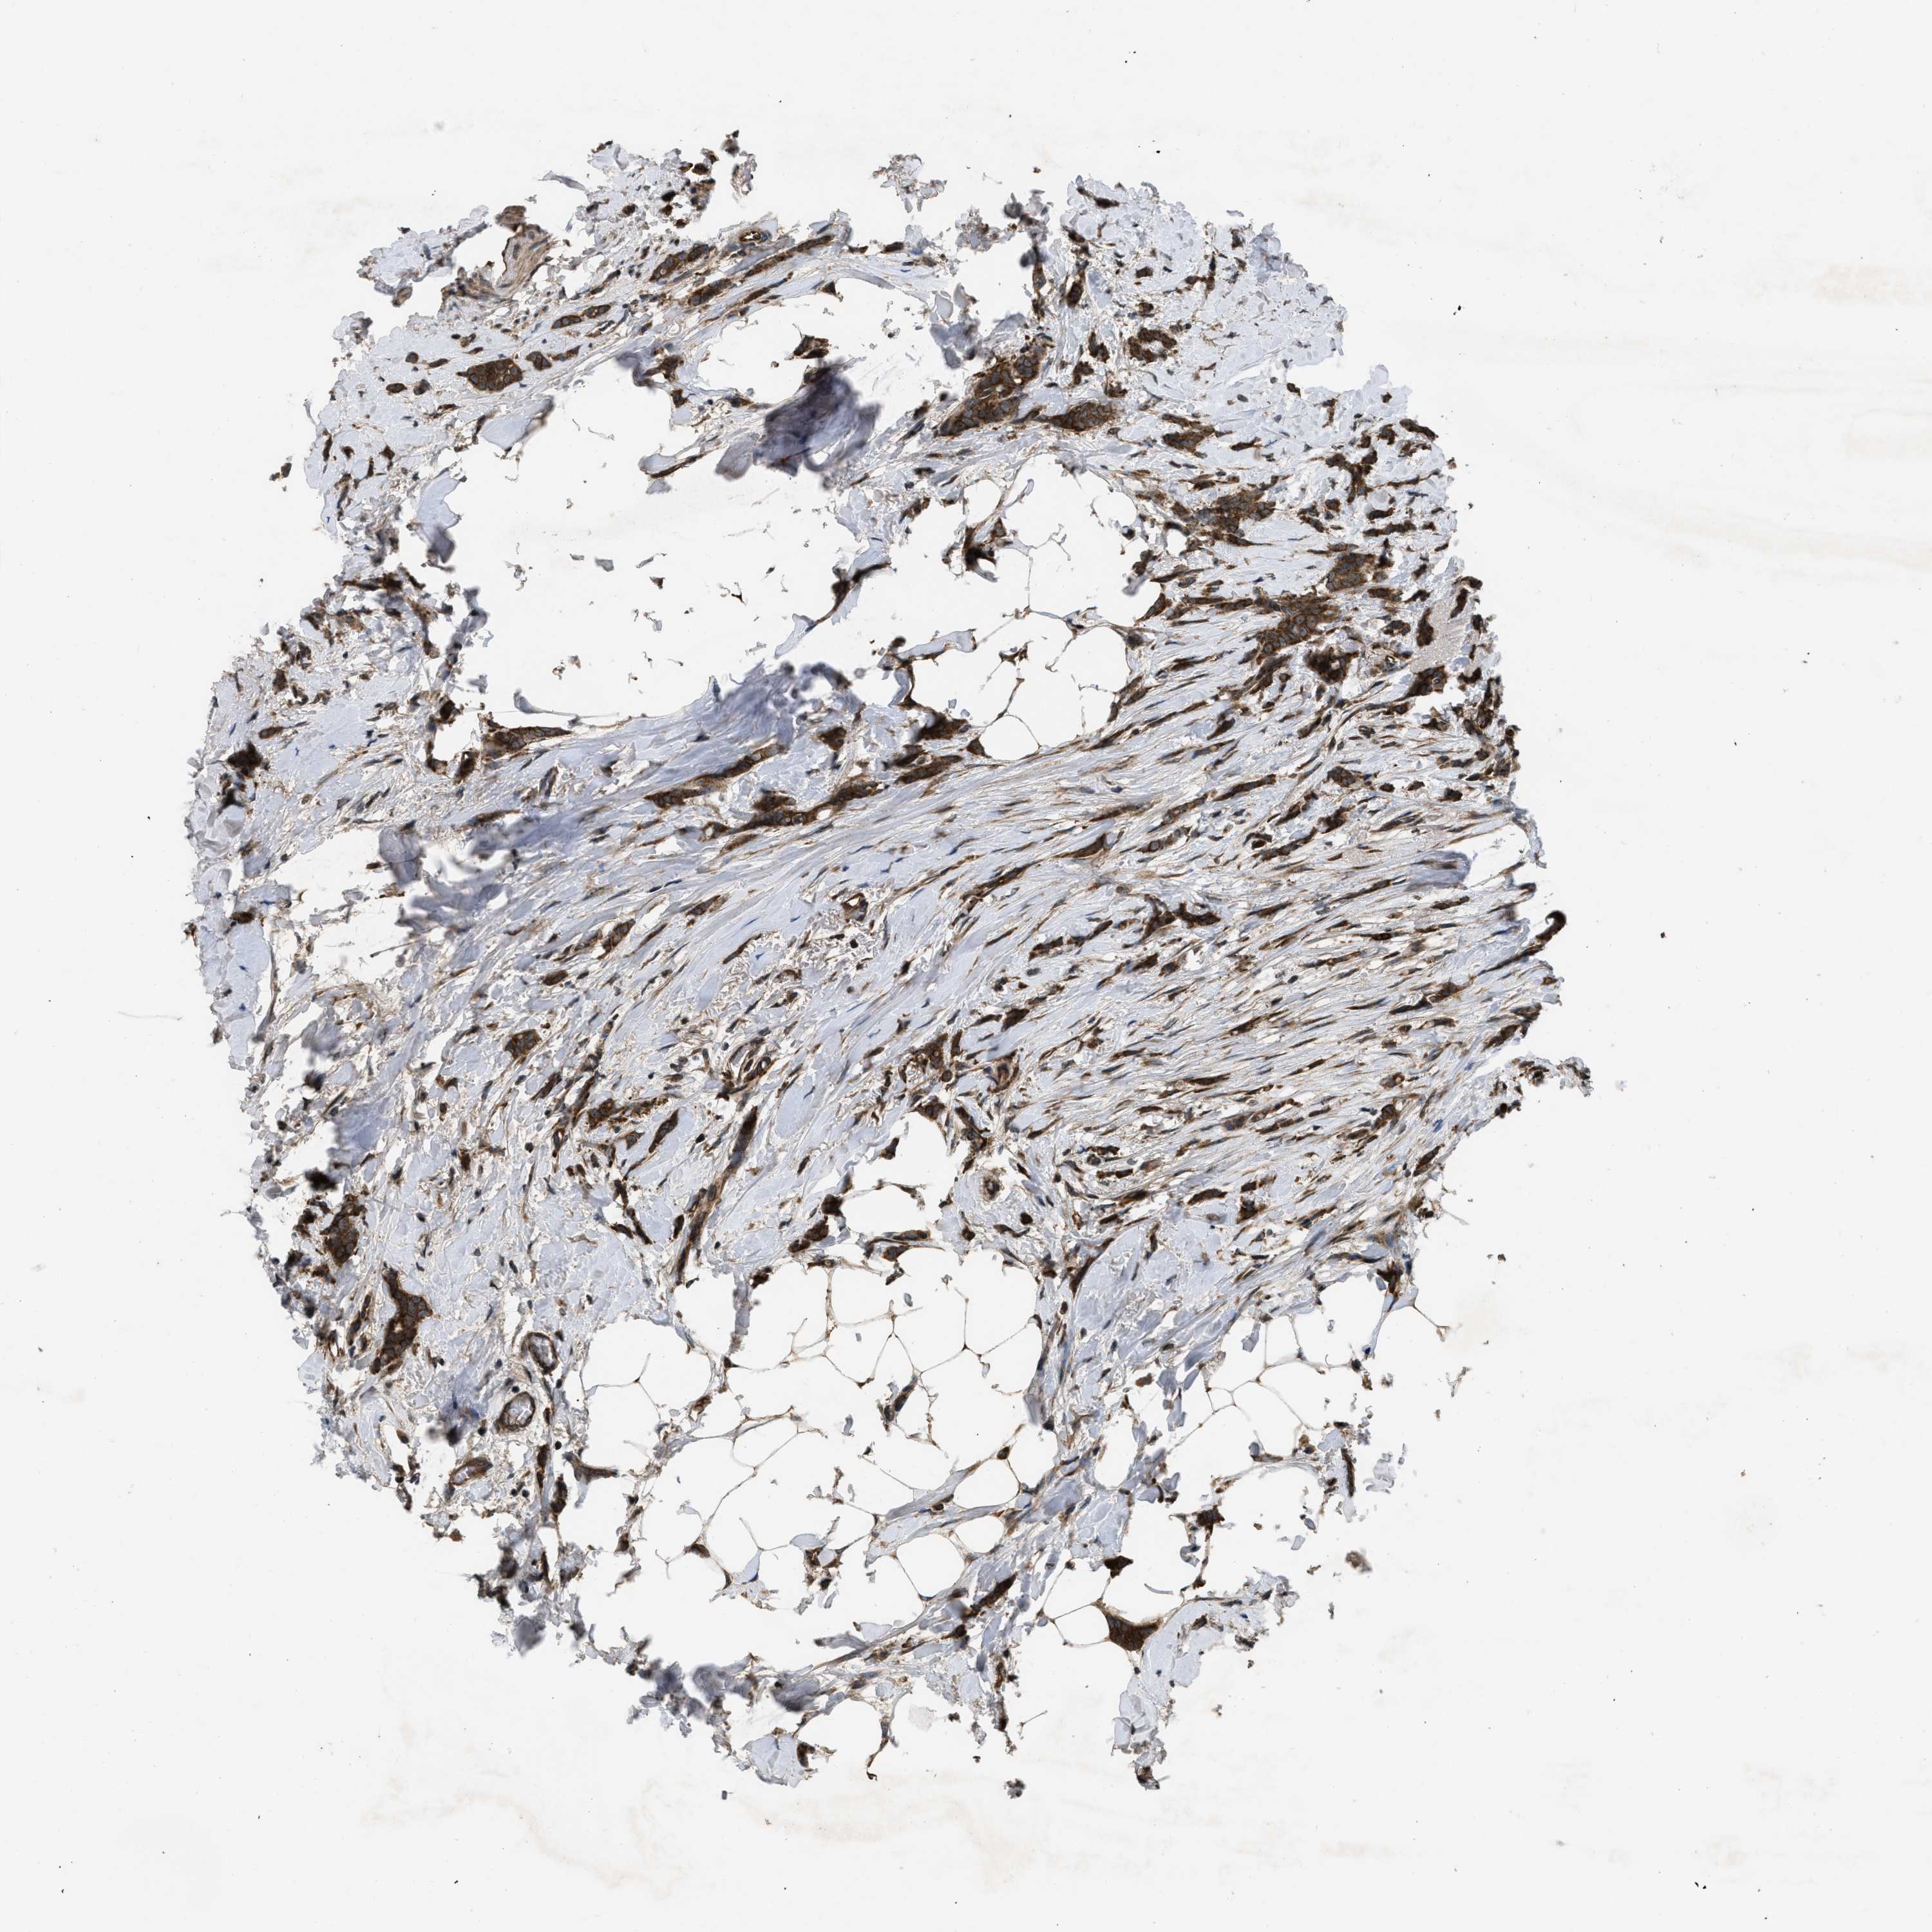

CANCER BREAST CANCER Show tissue menu

BRCA TCGA BRCA VALIDATION PROTEIN EXPRESSION

Breast cancer

Human cancer